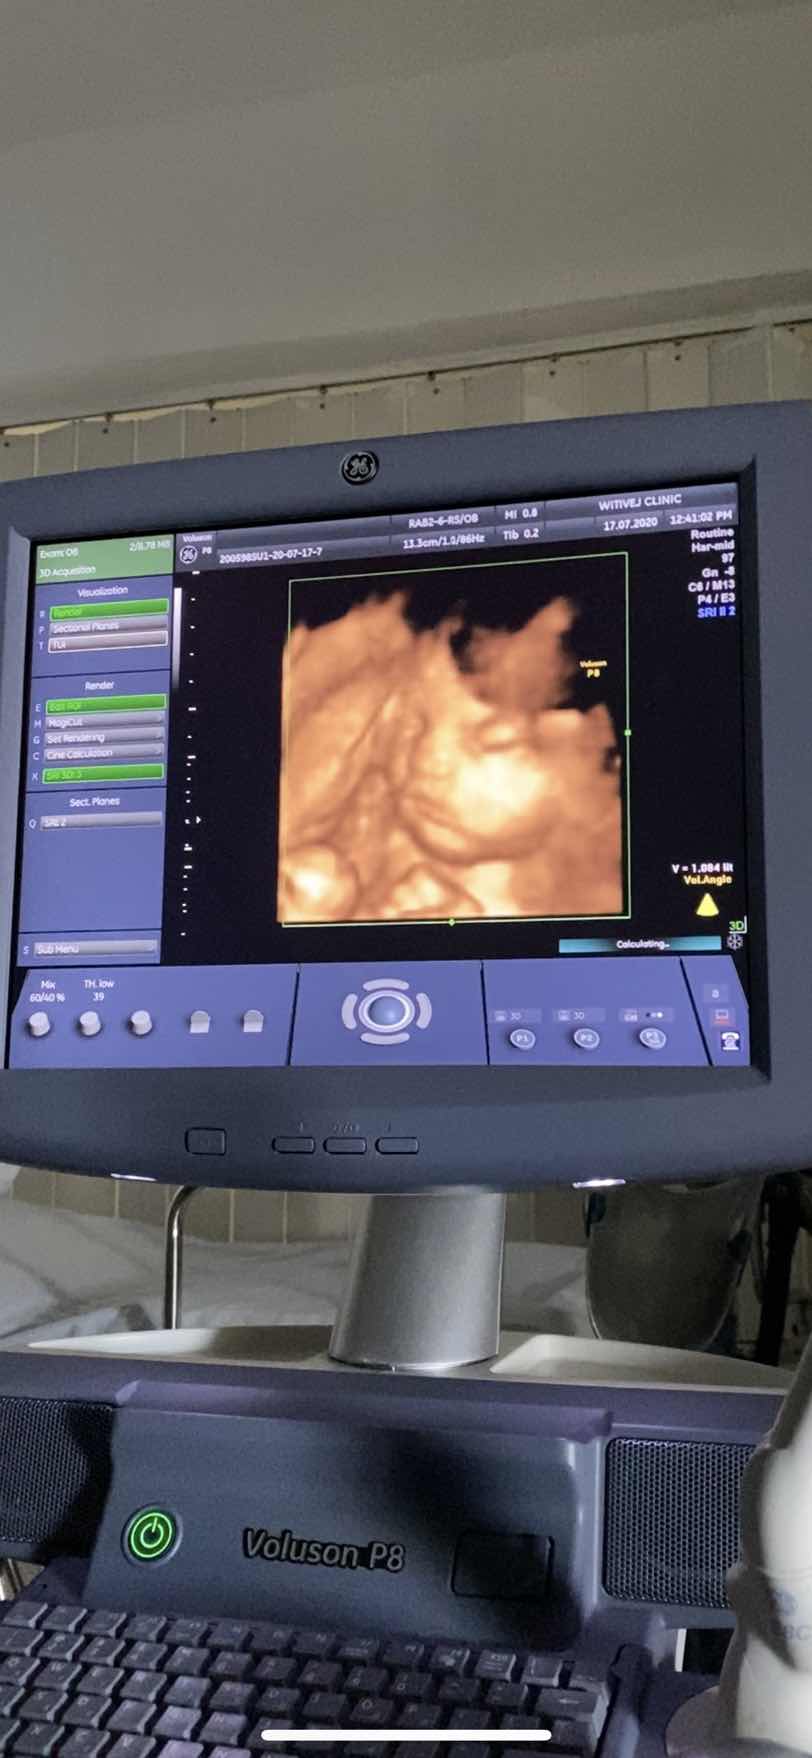

30 W ผุ้ชายคัปป๋ม

28 สัปดาห์ ครับ